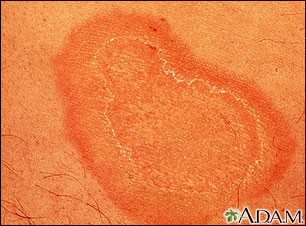

Erythema annulare centrifugum - close-up

When redness appears in ring shapes on the body, it is referred to as erythema annulare, shown here on the forearm. There are generally no symptoms, with the exception of mild itching (pruritus). It may be associated with serious diseases, but in the majority of cases, an underlying illness is never discovered.